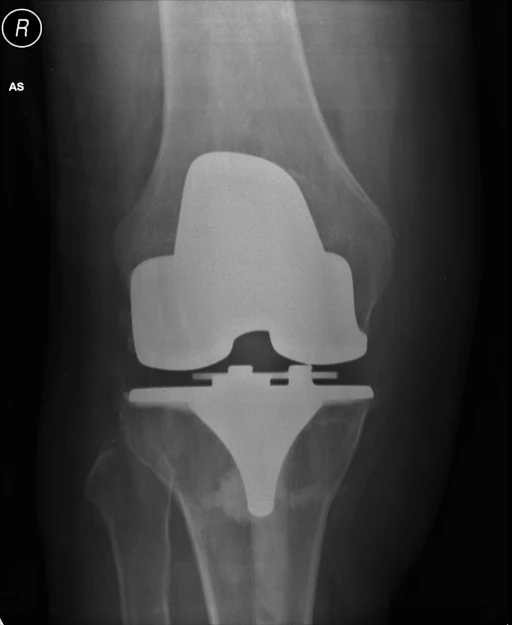

Predict the size of implant to be used during a patient’s total knee replacement surgery given that we know their demographic informations such as height, weight, age, gender, etc.

Successfully trained and deployed 8 models, 2 models each corresponding to Femur, Tibia, Tibial Insert and Patella (these are the bones that are replaced during knee surgery) Of the 2 models within each bone, one was used to predict the implant design and the other was used for size prediction.